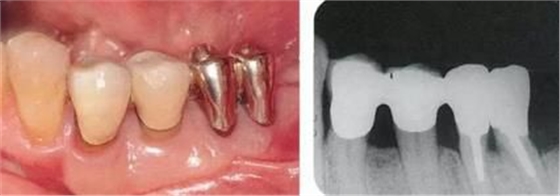

▲圖5-7,8

▲圖5-7 牙周外科處理后,使用臨時(shí)修復(fù)體將進(jìn)行了牙根分割處理的左下6兩根分離,為了提高根間的清潔性,使遠(yuǎn)中根朝遠(yuǎn)中方向傾斜。

▲圖5-8 配戴最終修復(fù)體后的側(cè)面照。獲得了足夠的附著齦。

▲圖5-9,10

▲圖5-9 配戴修復(fù)體9年后的狀態(tài)。探診值保持在2mm左右且沒(méi)有出血。

▲圖5-10 同時(shí)期X光片。骨組織平坦。